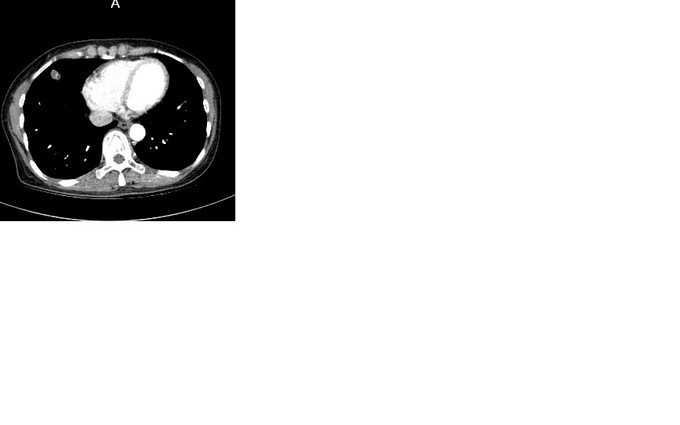

辅助检查:2015.7.31胸部CT(196593):右肺中叶炎症,右肺上叶多发肺大泡。2015.9.10胸部CT(200837):右肺中叶高密度灶,建议增强扫描;右肺上叶肺大泡。2015.9.16胸部增强CT:右肺中叶外侧段结节,恶性不除外,建议随访复查。右上肺肺气囊。右侧第5肋骨致密影。附见:肝脏膈面海绵状血管瘤考虑;肝脏囊肿。2015.9.11血常规:未见明显异常。入院后检查:09月19日心电图:窦性心律;正常范围心电图。09月19日超声:心脏:三尖瓣轻度返流,右侧甲状腺结节伴钙化,双侧颈动脉局部内膜增厚伴左侧斑块。09月19日 总IgE测定+降钙素原定量检测:免疫球蛋白E104.90IU/ml。09月19日 甲功全套+肿瘤系列(女7项)+生化分析(病房):肌酸激酶184IU/L,乳酸脱氢酶316IU/L,血管紧张素转化酶10IU/L,胆固醇6.15mmol/L,抗甲状腺球蛋白抗体77.76U/ml,铁蛋白304.0ng/ml,同型半胱氨酸17.97μmol/L,肾小球滤过率估值1121.17ml/(min*1.73m^2。09月21日 尿常规:尿潜血2+,结晶+个/LP,白细胞酶1+。09月19日 BNP、血液常规/HCRP、结核杆菌抗体、红细胞沉降率测定ESR、活化CD4细胞+活化CD8细胞+淋巴细胞亚群(T/B/NK、血流变、血凝/D二聚体、肿瘤系列(6项)、大便常规隐血、过敏源/IgE、呼吸道核酸检测、抗核抗体测定(ANA)+ENA谱+ANCA、荧光法病原体抗体:未见异常。09月22日咽拭子一般细菌/真菌/嗜血菌:未培养出嗜血杆菌,正常菌群,未培养出真菌。09月23日痰结核菌涂片:未找到抗酸杆菌。09月24日痰一般细菌/真菌/嗜血菌:未培养出真菌,未培养出嗜血杆菌,正常菌群。09月23日气管镜各级支气管通畅,刷片:(气管镜刷片)未见肿瘤细胞。灌洗液抗酸杆菌阴性,09月23日针吸涂片:(收到针吸涂片)未见肿瘤细胞。09月25日右肺结节:(右肺穿刺活检组织)肉芽肿性炎,倾向结核。

根据病理结果,诊断肺结核,转结核科治疗。 肺部孤立性结节的知识点就不贴了,大家都很了解了。下面说说自己的体会,看到病理结果我的心中是一万只草泥马飞过,这不符合预期啊。 本病例胸部CT一直提示恶性,孤立性结节,形状不规则,大于1cm,有毛刺,有中央钙化,有明显强化,不太符合结核的好发部位,也不符合结核的多病灶,多堆聚,多钙化,少肿块,少增强的特点,所以一直当恶性肿瘤来看待,对临床有一定的误导。经验是看胸部CT还是要再认真仔细点,多考虑不典型表现,多学习各种肿块的特点,多考虑各种可能,少点盲目自信。